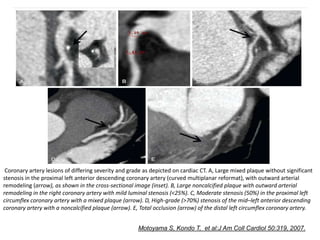

Coronary artery lesions of differing severity and grade as depicted on cardiac CT. A, Large mixed plaque without significant

stenosis in the proximal left anterior descending coronary artery (curved multiplanar reformat), with outward arterial

remodeling (arrow), as shown in the cross-sectional image (inset). B, Large noncalcified plaque with outward arterial

remodeling in the right coronary artery with mild luminal stenosis (<25%). C, Moderate stenosis (50%) in the proximal left

circumflex coronary artery with a mixed plaque (arrow). D, High-grade (>70%) stenosis of the mid–left anterior descending

coronary artery with a noncalcified plaque (arrow). E, Total occlusion (arrow) of the distal left circumflex coronary artery.

Motoyama S, Kondo T, et al:J Am Coll Cardiol 50:319, 2007.

Coronary artery lesionsof differing severity and grade as depicted on cardiac CT. A, Large mixed plaque without significant stenosis in the proximal left anterior descending coronary artery (curved multiplanar reformat), with outward arterial remodeling (arrow), as shown in the cross-sectional image (inset). B, Large noncalcified plaque with outward arterial remodeling in the right coronary artery with mild luminal stenosis (<25%). C, Moderate stenosis (50%) in the proximal left circumflex coronary artery with a mixed plaque (arrow). D, High-grade (>70%) stenosis of the mid–left anterior descending coronary artery with a noncalcified plaque (arrow). E, Total occlusion (arrow) of the distal left circumflex coronary artery. Motoyama S, Kondo T, et al:J Am Coll Cardiol 50:319, 2007.